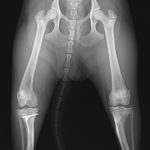

脛骨粗面剥離骨折

若くて、とても元気なワンコが椅子からジャンプした後に、後ろ足を着けなくなり、救急病院を受診したそうです。脛骨粗面剥離骨折が確定され、その後、主治医より骨接合術の依頼のため来院しました。

脛骨粗面が完全に脛骨より分離し、大腿四頭筋の牽引により、膝蓋骨が上方に変位していました。剥離した粗面を1.0mmのチタン合金製のWireで脛骨に再付着させました。(この若齢期において、テンションバンドの追加は禁忌とされています。)子犬にとっては辛いことですが、しばらくはサークルの中で安静が必要です。しかし、若いので早期に骨癒合することが期待されます。この部位の骨折は定期的に成長板へのダメージが生じていないか、X線検査でモニターしていく必要があります。